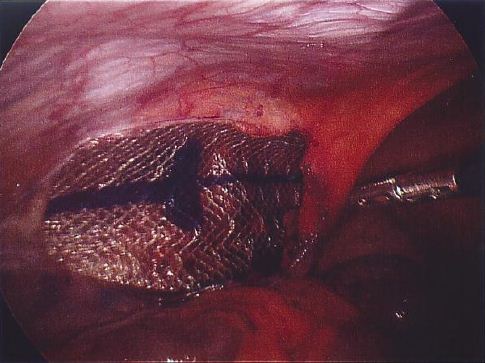

Infection while doing laparoscopic inguinal hernia repair. The infection was reluctant to heal with antimicrobial Though removal of the implanted mesh is ideal method of treatment in presence of infection as mesh acts as a foreign body .Our aim was to prevent a ... Fetch Here

Complications of Laparoscopic hernia repair. inadequate fixation with rolling up of the mesh and haematoma formation leading to infection. The treatment is supportive and incidence of all these complications is similar to that in conventional surgery. Future prospect of Laparoscopic ... Document Viewer